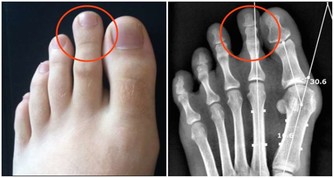

①生理病理需要:兒童、老人、孕婦及哺乳期婦女,以及有消耗性疾病如惡性腫瘤、肺部感染、瘧疾等患者,對某些維生素的需求超過常人。